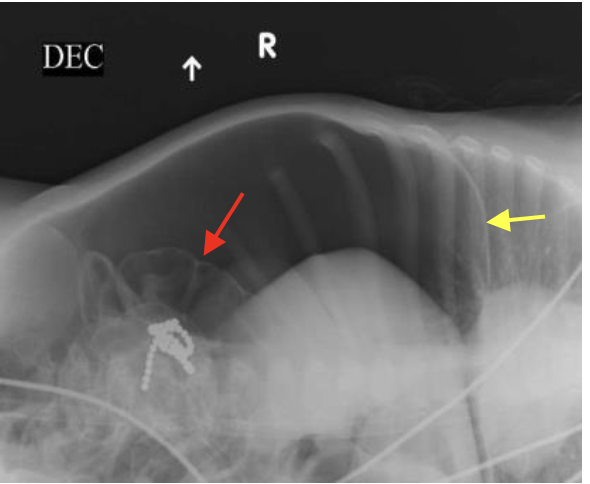

מה יש בחיצים?

צהוב- פס דקיק של הסרעפת

אדום- מעי, ניתן לראות את הדפנות בגלל שיש נוכחות חופשית של אוויר בחלל הבטן. למה יש נוכחות חופשית של חלל הבטן? כי ההורים הביאו יותר מדי ילדים וילד בלע שרשרת מגנטים שעשתה לו פרפורציה.